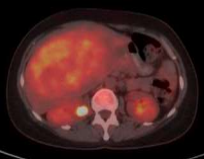

A 41-year-old woman was referred to our clinic with complaints of fever, good performance (Eastern Cooperative Oncology Group 1), no weight loss, no comorbidities, and no surgical history. Upon examination, there was a firm-to-hard, non-tender liver mass extending 13 cm below the right costal margin with rounded borders. All laboratory investigations, including liver function tests, viral markers, and tumour markers, were normal (alpha-fetoprotein< 1.3ng/mL). Abdominal multidetector computed tomography (Figure 1) revealed a normal liver size. The liver contours were smooth and the parenchymal density was normal. The hepatic vein, portal vein, and main branches were normal. The intrahepatic bile ducts were normal. A mass lesion, measuring approximately 15x11 cm, is observed near the level of liver segments V-VI-IVB, almost filling the space (HCC-fibrolamellar HCC?) No lymph nodes of abnormal size were observed in the abdomen. No significant free fluid is detected in the abdomen,The chest computed tomography findings were normal, the abdominal Magnetic resonance imaging  (MRI)(Figure 1) showed at the level of segments IVB-V-VI, there is a heterogeneously hyperintense lesion measuring 16.5x14.8x10.2 cm on T2-weighted images, The lesion shows peripheral enhancement predominantly in the early post-contrast phase, followed by  washout from the periphery in the delayed phase, with slightly increased enhancement in the centre, suggesting a possibility of fibrolamellar hepatocellular carcinoma (FH-HCC). The main portal vein and right portal vein branches were compressed by the identified lesion. A Positron Emission Tomography (PET) scan was performed, which revealed a hypermetabolic mass lesion in the liver, with no other lesions identified on the PET scan as the primary site (Figure 2). The primary diagnosis was fibrolamellar hepatocellular carcinoma (FL-HCC).

(Figure 2). A positron emission tomography (PET) scan revealed a hypermetabolic mass lesion in the right side of the liver.